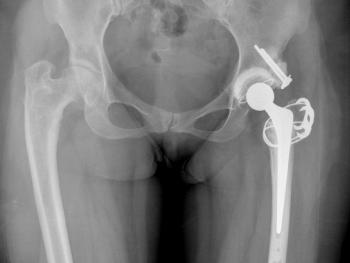

Figure 9 & Figure 10: DDH case – small socket – 40/22mm required. Leg length restored. Modularity of head sizes and offsets allows accurate restoration of leg length and offset.